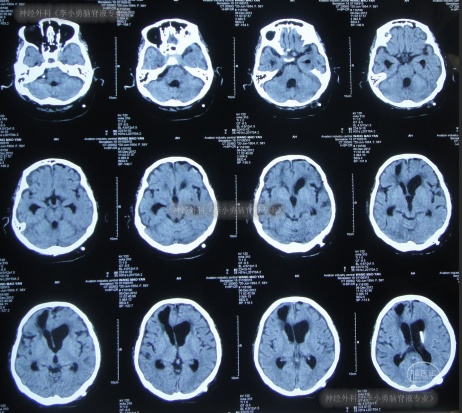

第2家医院出院1月余即2012年2月7日,夜里起夜突然又重复发作以前的症状(恶心呕吐、头昏),且比前2次发作严重,2012年2月8日住入第3家医院:呼和浩特市某三甲医院的神经外科治疗,入院查头颅CT(图-2)和MRI(图-3);脊髓核磁(图-4);肺部CT(图-5)及多次腰椎穿刺脑脊液化验检查(糖低、蛋白高),诊断为:结核性脑膜炎,脑积水。

图-2:2012年2月9日头颅CT